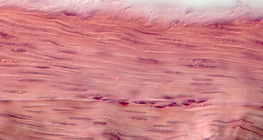

Grossissement de 1000 fois